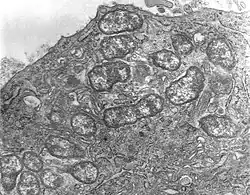

Orientia tsutsugamushi (del japonés tsutsuga "enfermedad" y mushi "insecto") es el agente causal de la fiebre de los matorrales o de la fiebre de los campistas,[1] siendo vectores y reservorio probablemente ácaros del género Leptotrombidium).[2][3] Es un parásito intracelular obligado, es decir que necesita infectar a una célula eucariota para multiplicarse. Es una bacteria gram negativa, aunque no se tiñe bien con la tinción de Gram, prefiriéndose la tinción de Giménez. Hay muchos serotipos descritos: Karp ( aproximadamente el 50% de todas las infecciones), Gilliam (25%), Kato (menos del 10%), y Kawasaki,[3][4] pero existe una enorme variabilidad, con ocho serotipos documentados en Malasia,[5] y otros muchos aún notificándose.[6][7][8] La infección con un serotipo no confiere inmunidad frente a otros serotipos (no hay inmunidad cruzada).

La bacteria fue en principio categorizada en el género Rickettsia,[1] pero actualmente está clasificada en un género aparte, Orientia, en el cual es la única especie.[9]

Mide 0.5 µm de ancho and 1.2 a 3.0 µm de largo. Es muy virulento y sólo puede ser manipulado en laboratorios con nivel de seguridad 3.[10]